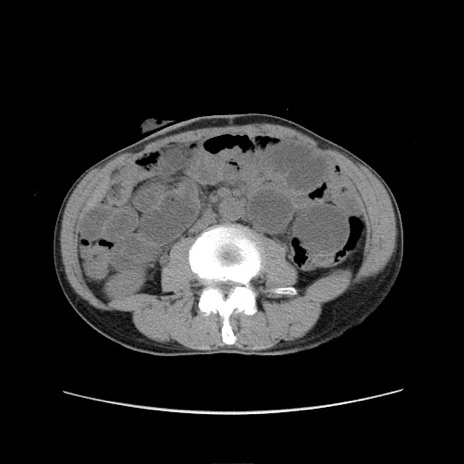

症例11(横断像)

【症例】 60歳代男性

【主訴】 下腹部痛

【現病歴】 本日夜中より下腹部痛の症状認め、受診。

【既往歴】 膀胱癌(膀胱全摘+尿管皮膚瘻術) 、胃癌術後

【身体所見】 BT 35.3℃、PR 58/min、BP 136/98mHg、腹部平坦、軟、腸蠕動音±、ストマ留置あり、左上腹部~正中部に圧痛あり、反跳痛なし。

【データ】WBC 5100、CRP0.01